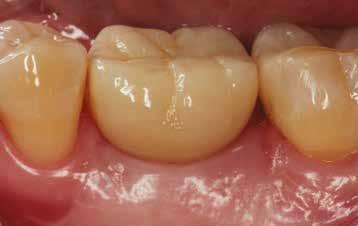

A kész korona átadásakor a páciens elégedett volt az esztétikával, az azóta eltelt évben rendszeres kontrollokon jelent meg, melyek során meggyőződtünk a kemény- és lágyszövetek stabilitásáról (18. és 19. képek).

17. a–b képek: A kész munka átadáskor. 18. a–c képek: 1 éves kontroll. 19. kép: Intraorális kontroll röntgen felvétele 1 évvel az átadás után.